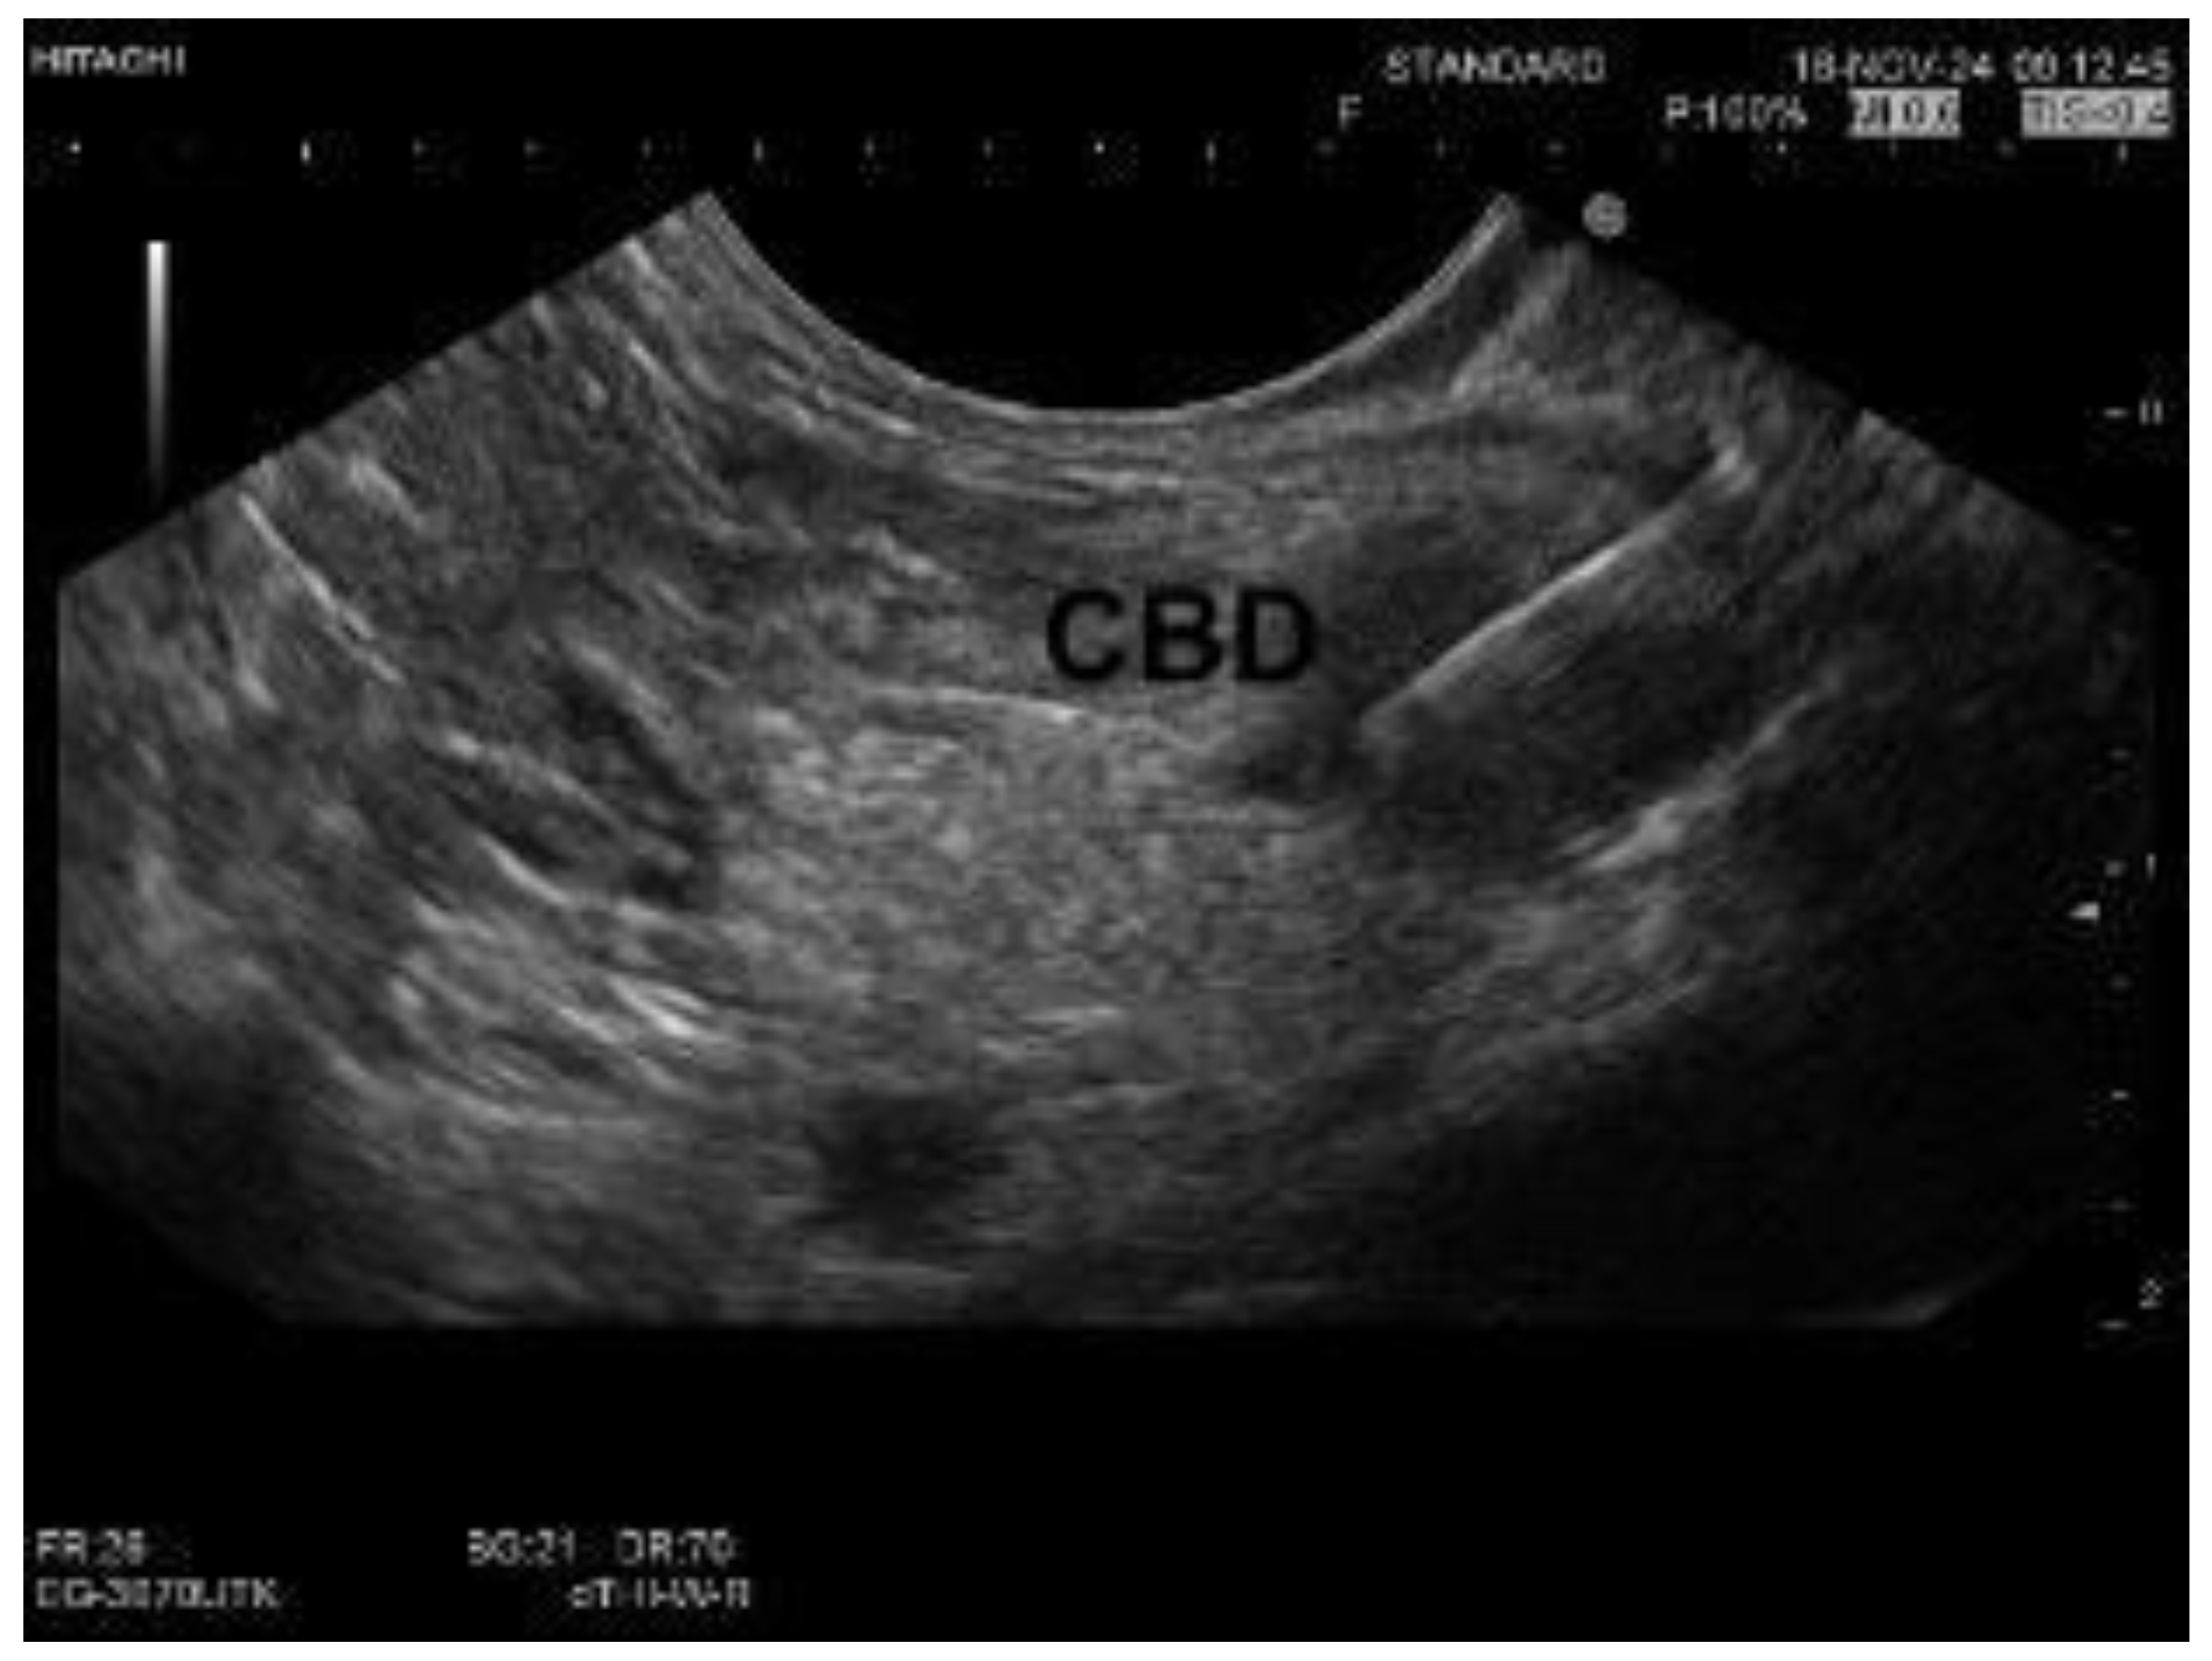

| Imaging Technique | Sensitivity (%) | Specificity (%) | Advantages | Limitations |

|---|---|---|---|---|

| Ultrasound | 31–100 | 71–97 | Cost-effective, accessible, non-invasive | Limited in differentiating stricture origin |